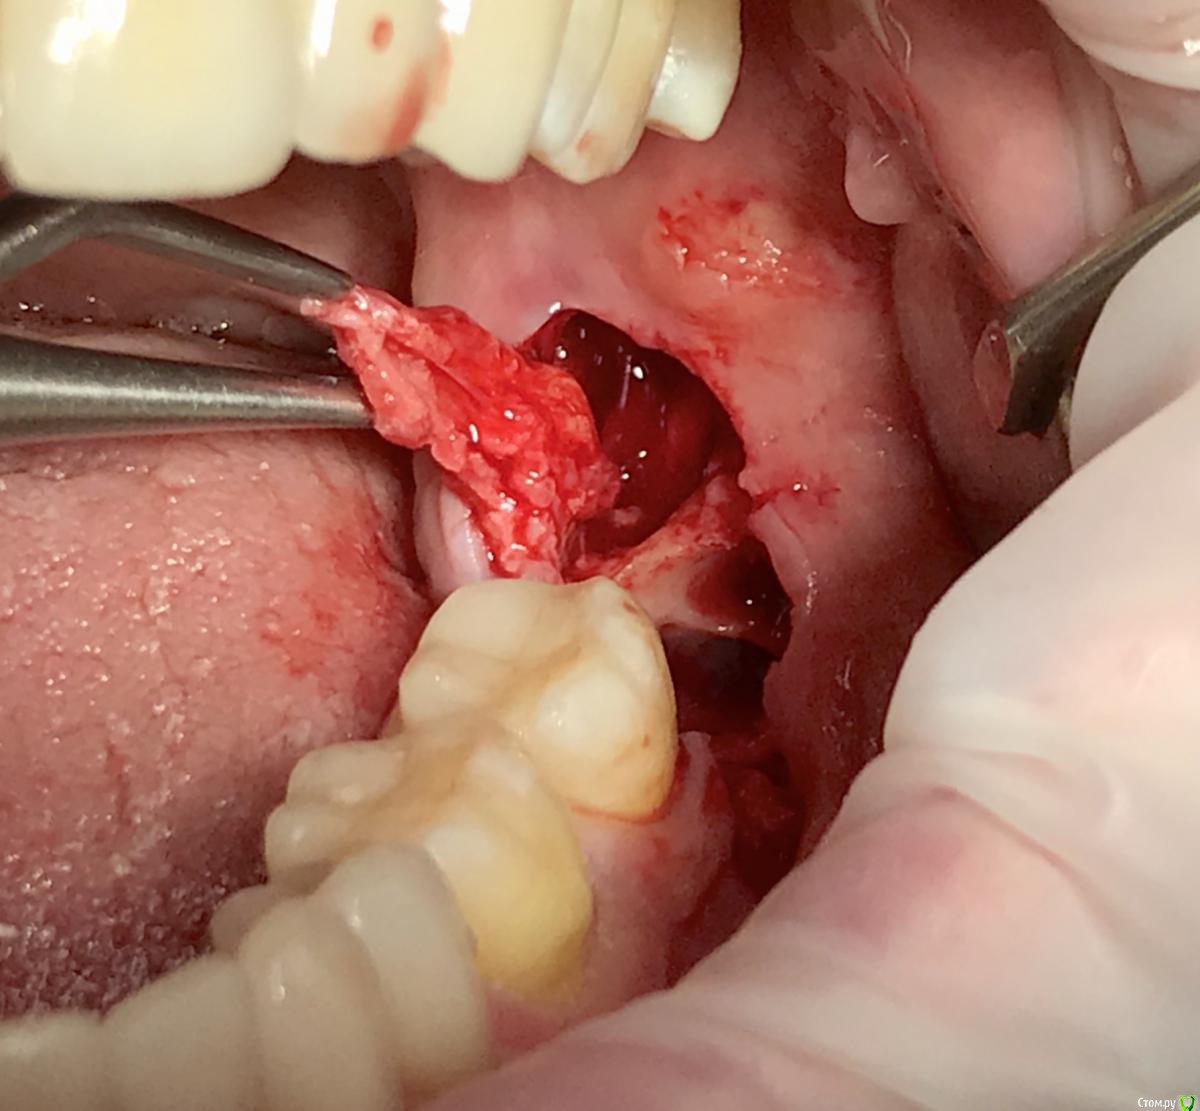

колесников Опубликовано 1 апреля, 2018 Автор Поделиться Опубликовано 1 апреля, 2018 (изменено) Бытует мнение,что капсулу фолликула ретенированой 8ки надо удалять . полностью и тщательно. Аргументов я уже не помню,вроде бы как она стремительно гранулирует,затрудняя регенерацию лунки и кажется что то подобное было у меня в начале практики,что я поверил в эту теорию. Но капсула из этого клин случая ,своей плотностью ,эластичностью и крепостью прикрепления язычно,толкнула меня на эксперимент использовать ее в качестве покровного материала. Протокол был обычный :сепарация и экстракция моляра,графт в лунку (1 г), далее вместо ретромолярно язычного лоскута-капсула фолликула (не фиксировалась,т.к. легла без натяжения) ,края сопоставлены и ушиты. Течение без симптомное. Через неделю: открывание рта не затруднено, слизистая без признаков воспаления. Прогнозируемо щелевидное расхождение краев в первой трети,но при зондировании все плотно и эпителизировано. Как обычно 1 визит,но течение без сопутствующих дискомфортных ощущений. Случай единичный,но результат мне понравился,если будут соответствующие условия- стану использовать Изменено 1 апреля, 2018 пользователем колесников 2 Ссылка на комментарий

колесников Опубликовано 4 апреля, 2018 Автор Поделиться Опубликовано 4 апреля, 2018 Еще вариант перекрытия графта -фиброзные грануляции однтогенного очага 1 Ссылка на комментарий